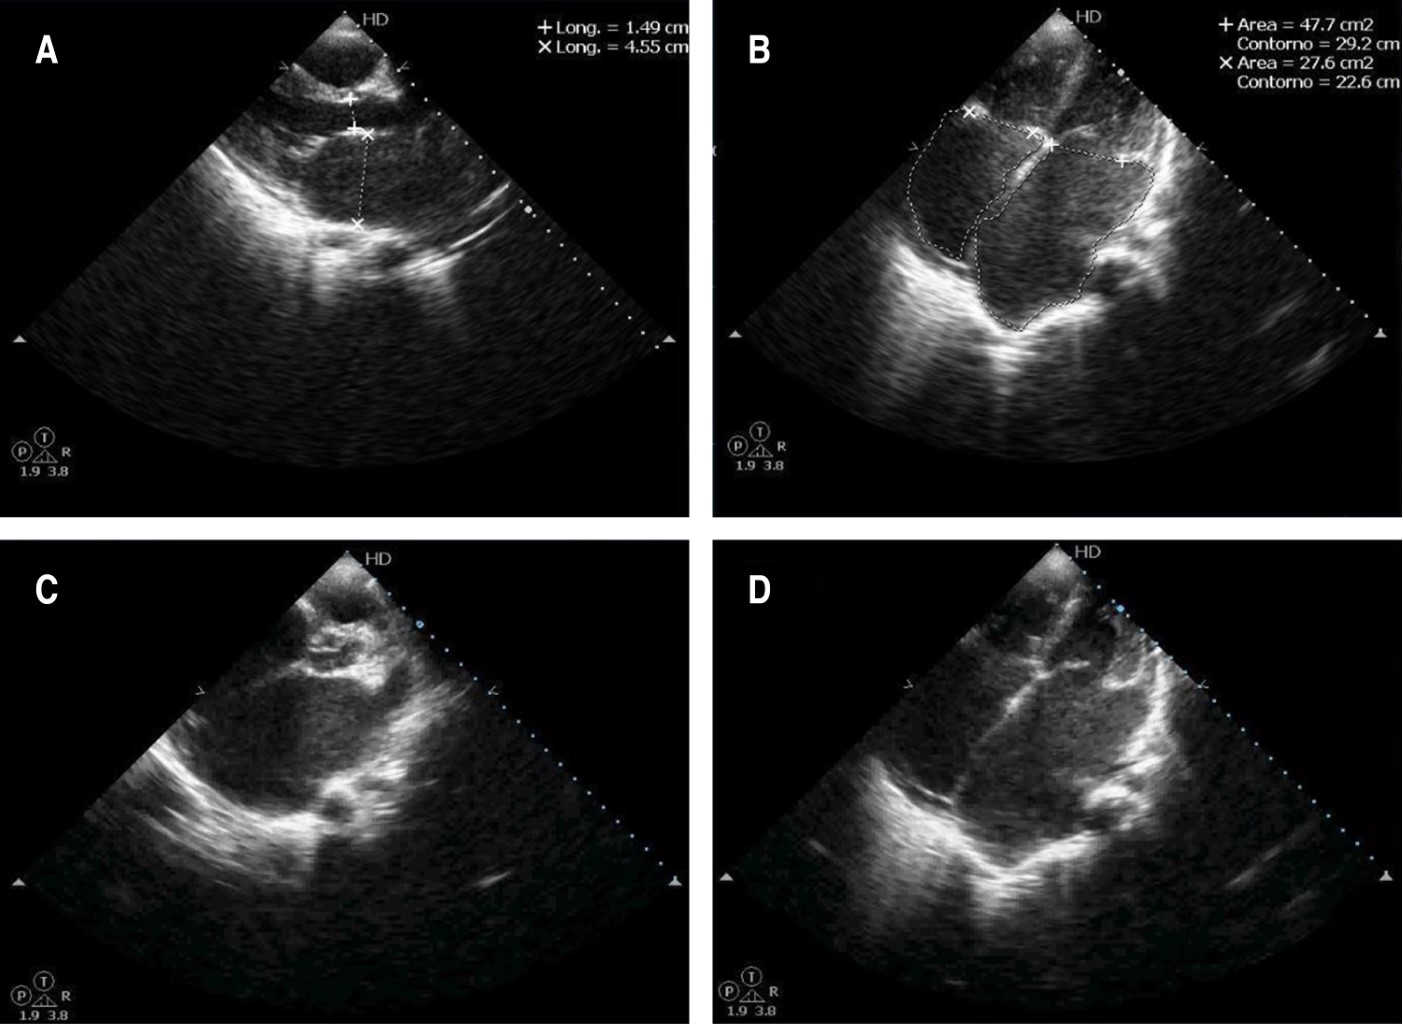

One of the first-degree relatives of the patient had genetic investigations which reported a heterozygous mutation in gene TNNI3, classified as a variant of uncertain significance associated with Dilated cardiomyopathy 2A (OMIM:611880), Dilated cardiomyopathy 1FF (OMIM: 613286), Restrictive cardiomyopathy familial 1 (OMIM: 115210), Hypertrophic cardiomyopathy 7 (OMIM: 613690), all of which have an autosomal dominant inheritance pattern. A diagnosis of cardiomyopathy was suspected due to the clinical presentation and family history. Findings in the initial chest X-ray (Figure 1) revealed cardiomegaly, bilateral atrial enlargement, and pulmonary congestion, and those on the ECG (Figure 2) showed a sinus rhythm, bilateral atrial enlargement, and right ventricle strain supported the suspected diagnosis. The echocardiogram (Figure 3) confirmed the bilateral atrial dilation (LA; 34.8 cm2, RA: 34.1 cm2), an E/A ratio greater than 2, and a PSAP of 47 mmHg, and a left atrial volume of 154 cm3. Using the recommendations for chamber quantification by the European Society of Cardiology, those values were classified as severely abnormal as the atrial volume was above 73 mL. Therefore, indicating severe damage to the left atrium. Abdominal ultrasound confirmed hepatomegaly with dilation of suprahepatic veins. PCR SARS-CoV-2 was negative.

The patient's X-rays, combined with clinical findings, confirmed a global cardiac illness. The electrocardiogram revealed the presence of atrial hypertrophy, which led to echocardiography to determine atrial involvement and measure how much this impacted cardiac function. The echocardiogram reported an atrial diameter of 45.5 mm and an area of 47.7 cm2. According to the European Society of Cardiology,15 the patient had a severe compromise of both her left and right atria. Even though the FEV was not affected, the E/A ratio showed a restrictive filling pattern due to the atrial compromise. In conclusion, a diagnosis of restrictive cardiomyopathy was an adequate diagnosis according to both clinical and echocardiographic data.

Figure 3